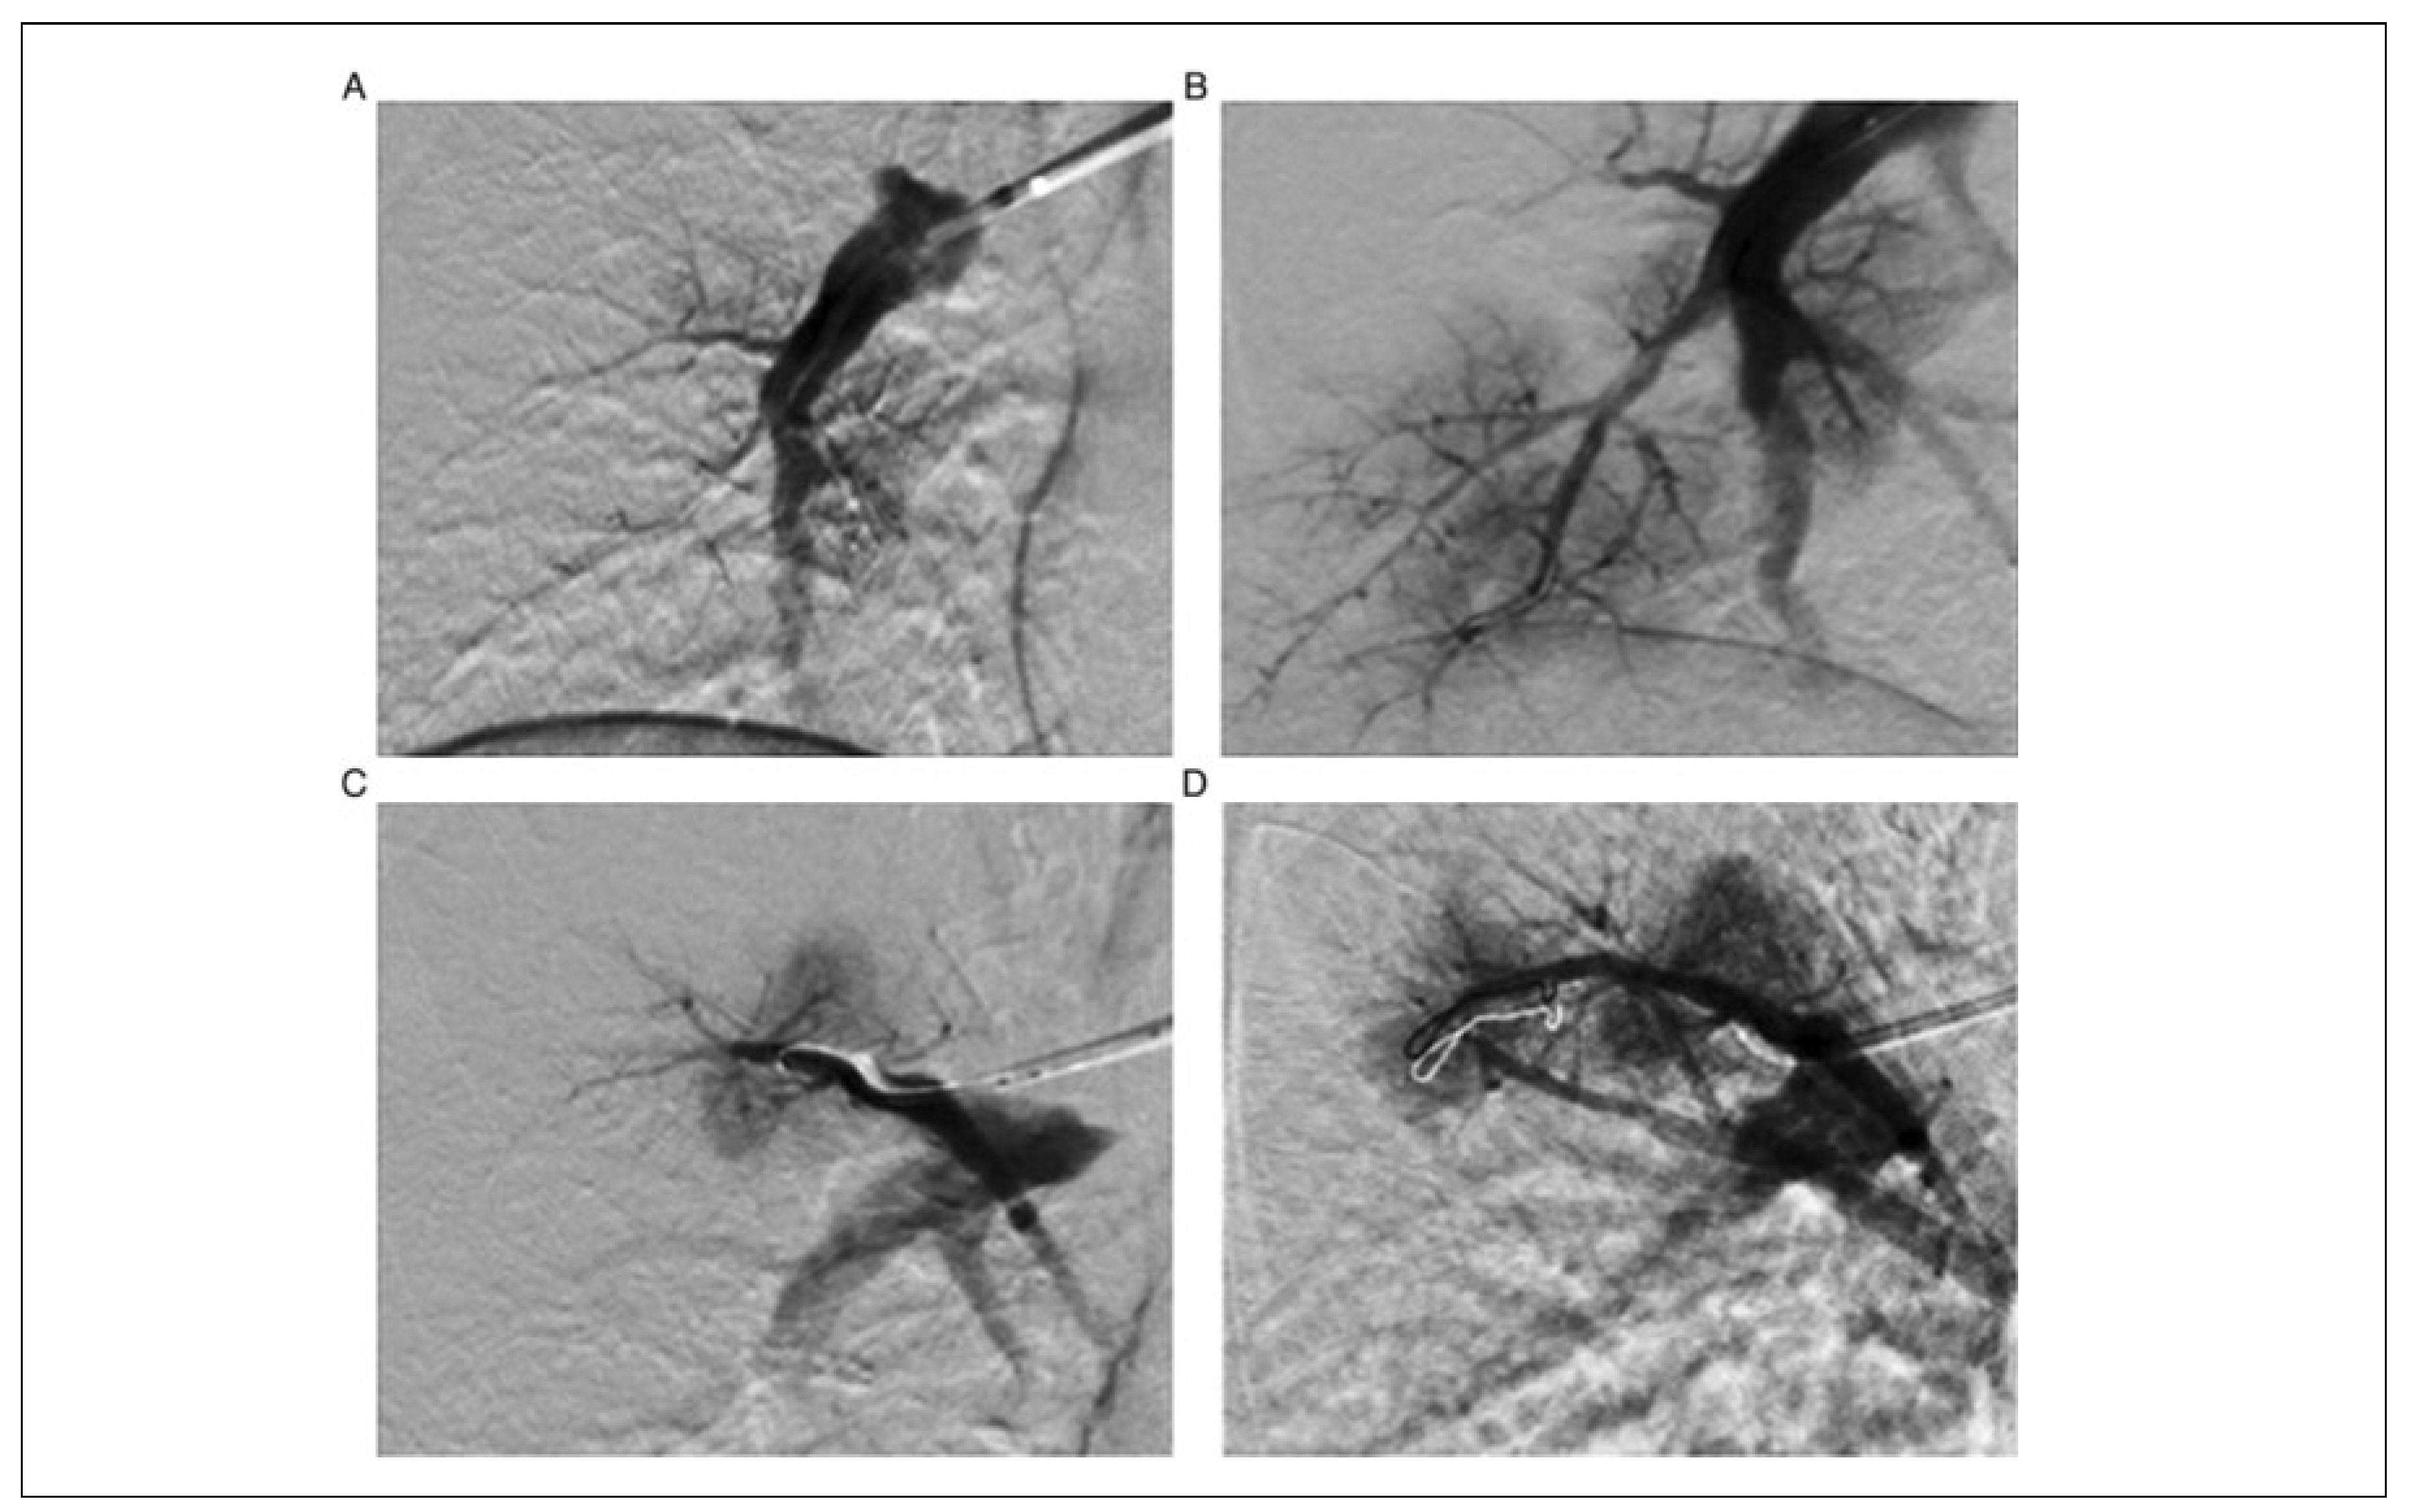

Percutaneous Pulmonary Angioplasty

Percutaneous Pulmonary Angioplasty in Chronic Thromboembolic Hypertension: Indications and Outcome